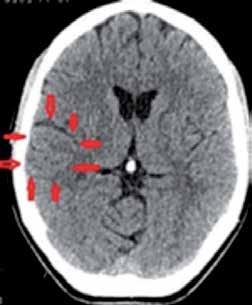

»Moje meritve kažejo, da so pri ženskah drobne žilice vedno slabše kot pri moških. In teh arteriol je ogromno – na sliki lahko vidimo, kako veliko jih je denimo v glavi. To razloži, zakaj je demence več pri ženskah kot pri moških. Tudi revmatoidnega artritisa in skleroze,« pojasnjuje.

Razširjenost bolezni, povezanih s slabo prekrvitvijo arteriol, pri ženskah (temni del) v primerjavi z moškimi (svetli del).

Tako zelo je naše telo prepredeno z majhnimi žilicami ali arteriolami.